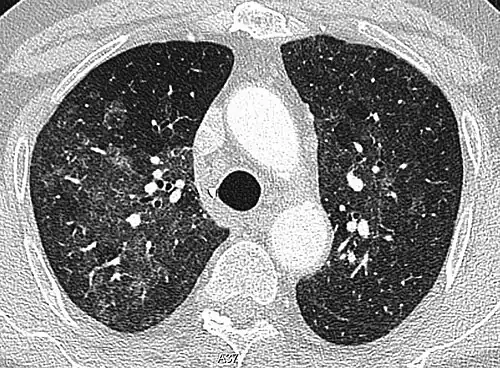

High-Resolution CT image in a patient with Pneumocystis pneumonia infection showing ground-glass opacities.

The diffuse pattern typically refers to GGOs in multiple lobes of one or both lungs. Broadly, a diffuse pattern of GGO can be caused by displacement of air with fluid, inflammatory debris, or fibrosis. Cardiogenic pulmonary edema and ARDS are common causes of a fluid-filled lung. Diffuse alveolar hemorrhage is a rarer cause of diffuse GGO seen in some types of vasculitis, autoimmune conditions, and bleeding disorders.[6]

Inflammation and fibrosis can also cause diffuse GGOs. Pneumocystis pneumonia, an infection typically seen in immunocompromised (e.g. patients with AIDS) or immunosuppressed individuals, is a classic cause of diffuse GGOs. Many viral pneumonias and idiopathic interstitial pneumonias can also lead to a diffuse GGO pattern. Radiation pneumonitis, a side effect of pulmonary radiation therapy, can lead to pulmonary fibrosis and diffuse GGOs.[6]